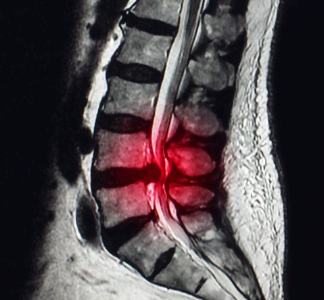

추간판은 흔히 말하는 디스크로 말랑한 연골 구조물이라고 생각하시면 됩니다. 이것은 척추뼈끼리 부딪히는 것을 막아주는 중요한 역할을 하는데 이런 추간판이 탈출하면서 신경을 누르게 되어서 나타나는 증상이 바로 추간판 탈출증 증상입니다.

추간이라는 것은 척추 사이라는 뜻이고 척추뼈 사이 말랑한 연골 뼈는 추간판으로 둥근 판의 모양을 하고 있습니다. 뼈 사이의 탄력을 담당하는 것으로 이것이 너무 심하게 눌리거나 이상이 생기면 추간판이 돌출되면서 문제가 생기게 되는데요. 그러면 추간판 탈출증 증상에 대해서 알아보도록 하겠습니다.